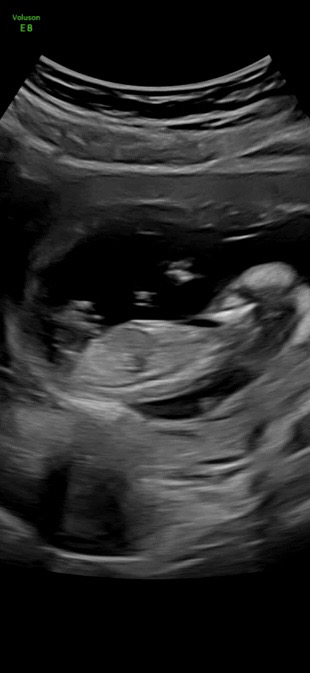

12주 4일 입니당 각도법 참견 마구마구 해주세요.